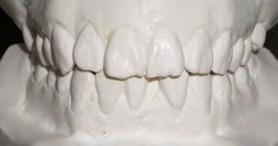

52 | SONRIENDO AL FUTURO

Tratamiento ortodóncico en paciente adulto tratado con extracciones de primeros molares permanentes. Reporte de caso

en paciente adulto tratado con extracciones de primeros molares permanentes. Reporte de caso

Dentista y Paciente 52 Sonriendo al futuro